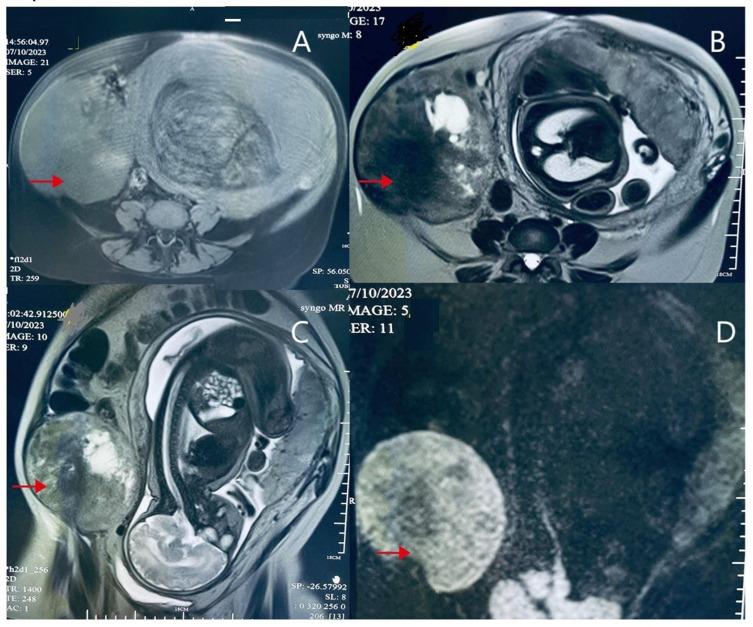

Pregnancy-Associated Giant Abdominal Desmoid Tumor: A Case Report of Active Surveillance and Surgical Management.

This case describes a pregnant woman with a suspected desmoid fibromatosis tumor who refused termination of pregnancy, opting for close monitoring until late gestation and successfully delivering a healthy baby.